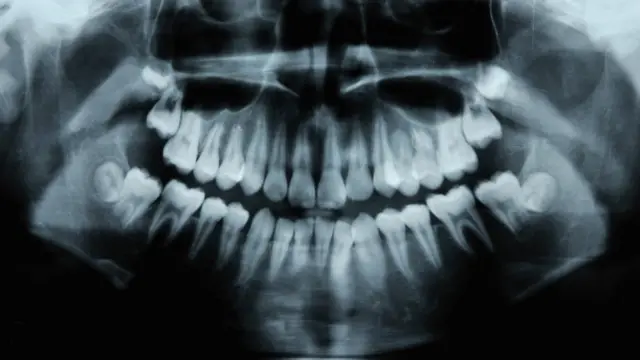

La periodontitis o enfermedad de las encías, es la segunda enfermedad oral más extendida después de las caries, y afecta a más del 47% de los adultos mayores de 30 años.

A partir de los 65 años, el 64% tiene periodontitis moderada o grave. A nivel mundial, es la undécima enfermedad más común en el mundo.

La periodontitis es una infección que no se encuentra en la superficie de las encías que se pueden ver cuando sonríes, sino que se encuentra muy por debajo de la superficie.

Después de una fase inicial de inflamación superficial en la parte visible de la encía (gingivitis), las bacterias descienden por debajo de la línea de las encías hacia bolsas cerca de la raíz del diente donde erosionan las estructuras que mantienen al diente en su lugar.

Debido a la naturaleza oculta de la periodontitis, muchas personas que la padecen no saben que está ahí hasta sus etapas muy avanzadas. La enfermedad tiene un componente genético, y también está influenciada por la higiene bucal.